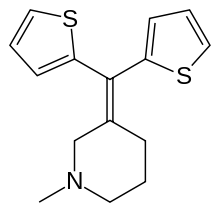

The pharmacodynamic response to an opioid depends upon the receptor to which it binds, its affinity for that receptor, and whether the opioid is an agonist or an antagonist. For example, the supraspinal analgesic properties of the opioid agonist morphine are mediated by activation of the μ1 receptor; respiratory depression and physical dependence by the μ2 receptor; and sedation and spinal analgesia by the κ receptor. Each group of opioid receptors elicits a distinct set of neurological responses, with the receptor subtypes (such as μ1 and μ2 for example) providing even more [measurably] specific responses. Unique to each opioid is its distinct binding affinity to the various classes of opioid receptors (e.g. the μ, κ, and δ opioid receptors are activated at different magnitudes according to the specific receptor binding affinities of the opioid). For example, the opiate alkaloid morphine exhibits high-affinity binding to the μ-opioid receptor, while ketazocine exhibits high affinity to ĸ receptors. It is this combinatorial mechanism that allows for such a wide class of opioids and molecular designs to exist, each with its own unique effect profile. Their individual molecular structure is also responsible for their different duration of action, whereby metabolic breakdown (such as N-dealkylation) is responsible for opioid metabolism.

There are a number of broad classes of opioids:[260]

Tramadol and tapentadol, which act as monoamine uptake inhibitors also act as mild and potent agonists (respectively) of the μ-opioid receptor.[264] Both drugs produce analgesia even when naloxone, an opioid antagonist, is administered.[265]